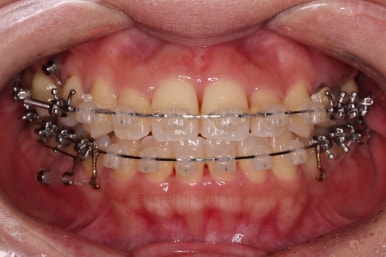

환자분이 선택하신 장치는 데이몬 클리어라고 하는 자가결찰 세라믹 장치입니다.

자가결찰 세라믹 중에 가장 심미적으로 우수한 장치가 데이몬 클리어인데요.

철사를 제외한 모든 파트가 세라믹으로 되어있습니다.

장치를 부착한 모습 참고해 주시고요.

아랫니는 중앙선을 맞추기 위해서 미니스크류를 이용해 한 쪽으로 당기는 중이고요.

이 과정에서 아랫니들이 약간은 뒤로 들어가져서 아랫입술 부위의 돌출감을 아주 약간은 줄일 수 있습니다.

윗니 임플란트 할 자리는 적절히 계속 맞춰줍니다.

중앙선도 점점 맞아지고 있어요.